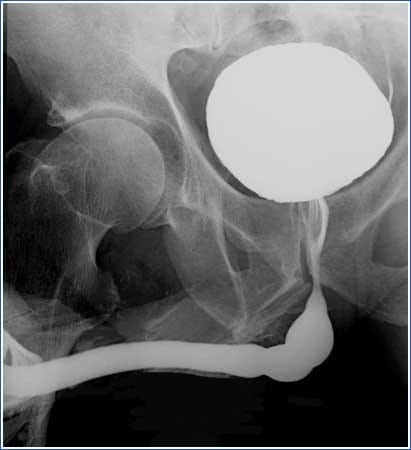

Étude ciblée du bas appareil urinaire (vessie et urètre) pour rechercher des anomalies de la miction, des rétrécissements urétraux ou un reflux vésico-rénal.

Examen de référence du bilan de fertilité permettant la visualisation de la cavité utérine et la vérification de la perméabilité des trompes de Fallope (recherche d'obstructions, polypes ou malformations).

Bilan fonctionnel et morphologique complet de l'arbre urinaire, visualisant la sécrétion des reins et l'écoulement de l'urine jusqu'à la vessie pour détecter calculs ou blocages.